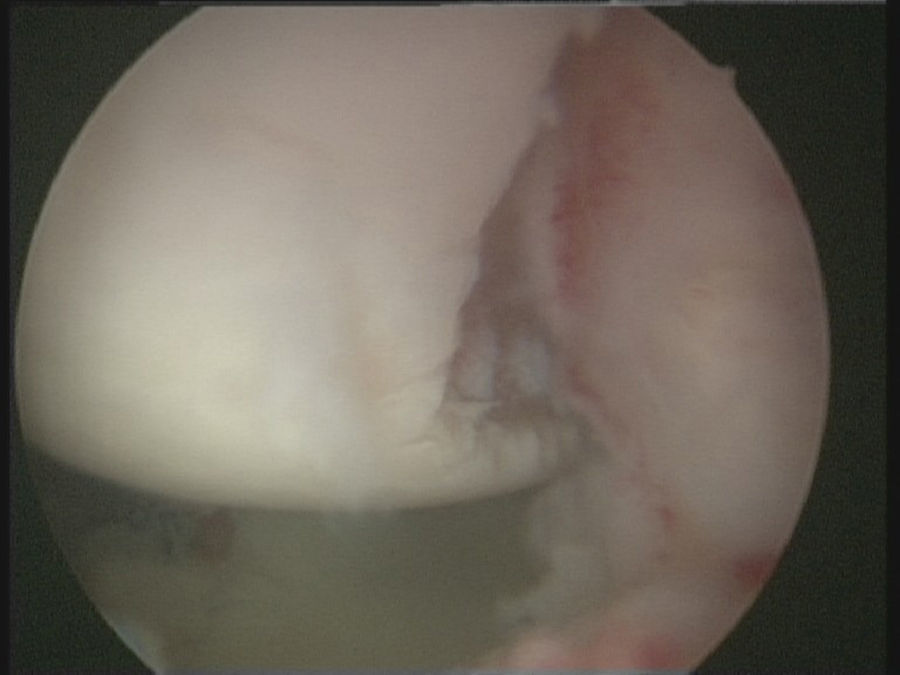

Técnica quirúrgicaBajo anestesia general y locorregional (bloqueo interescalénico), se intenta reducir el hombro de forma cerrada. En caso de no conseguirlo se coloca al paciente en decúbito lateral con tracción de unos 5kg y, siguiendo la técnica descrita por Verma5, se introduce un «Wissinger» por el portal posterior estándar, el que empleamos para la artroscopia de hombro. Con el «Wissinger» a través del portal realizamos tracción de la cabeza humeral hacia lateral, apoyándonos en la cápsula y en la parte posterior del manguito, no en el hueso. Habitualmente con esta maniobra conseguimos introducir la cabeza humeral en la glenoides y podemos pasar a realizar la artroscopia de hombro. En caso de no conseguir una reducción, pasaríamos a realizar una reducción abierta con el paciente en posición de silla de playa y con una vía de abordaje anterior al hombro. Con el hombro reducido se realiza la artroscopia de hombro. Se emplean los portales posterior, anterosuperolateral, anterior, portal de Wilmington y portal posteroinferior. Se estudia la lesión de Hill-Sachs inverso, la relación con el tendón del subescapular y la lesión del labrum posterior (fig. 2, figs. 3 y 4), el resto del labrum y el manguito de los rotadores. Hay que limpiar bien la articulación, extirpar todo el tejido fibroso, liberar el labrum posterior de las adherencias a la glena, preparar el lecho óseo de la glena antes de colocar los implantes (en el caso 1 se emplearon 2 implantes Lupine BR [DePuy Mitek, Raynham, MA], y el caso 2 con un Gryphon BR [DePuy Mitek, Raynham, MA] cargado con doble sutura), realizar la reconstrucción capsulolabral con un pasador directo o indirecto, anudar y cortar las suturas. Una vez reparadas las lesiones soltamos el brazo del sistema de tracción y comprobamos la relación de la cabeza humeral, del defecto óseo anterior con la glenoides, al hacer rotaciones del hombro (sobre todo si hay riesgo de «enganche» con la rotación interna), y decidimos si fijamos el tendón del subescapular en el defecto óseo humeral anterior, tal y como describió Krackhardt6.

No es estrictamente necesario que reproduzcamos un enganche de la lesión de Hill-Sachs inversa para decidir realizar el remplissage inverso. Con la óptica en el portal anterosuperolateral liberamos el tendón del subescapular, su cara anterior y posterior. Preparamos el lecho óseo de la cabeza humeral, extirpando todo el tejido fibroso de la lesión de Hill-Sachs inversa, con el sinoviotomo, la fresa de hueso o periostotomos, hasta obtener hueso sangrante. Entonces desde el portal anterior, insertamos los implante en el defecto óseo (en el caso 1 un 5,5 Healix BR [DePuy Mitek, Raynham, MA] con 2 suturas UHMWPE [Orthocord; DePuy Mitek]) en el tercio superior y en la zona más medial del defecto (fig. 5), y en el caso 2 insertamos 2 Gryphon BR Healix BR (DePuy Mitek, Raynham, MA) con 2 suturas UHMWPE (Orthocord; DePuy Mitek), uno inferior y otro superior en la zona más medial del defecto óseo. Recuperaremos las suturas desde un portal anterosuperior accesorio y con una pinza para atravesar el tendón (Penetratror DePuy Mitek, Raynham, MA) a través del portal anterior, atravesamos el tendón del subescapular y recuperamos las suturas. Daremos puntos colchoneros, uno inferior y otro superior, para conseguir un buen contacto del tendón con el hueso, separando los puntos entre 1 y 2cm (fig. 6). Podemos ayudarnos con un empujanudos a través del portal anterosuperior accesorio para el manejo y recuperación de las suturas, acercándolas a la boca de la pinza penetrator, tratando de no mover en exceso la pinza una vez atravesado el tendón, para evitar lesionar el tendón y el cartílago. Manteniendo el brazo en 35-40° de rotación interna anudamos primero el punto inferior y luego el superior (figs. 7 y 8).